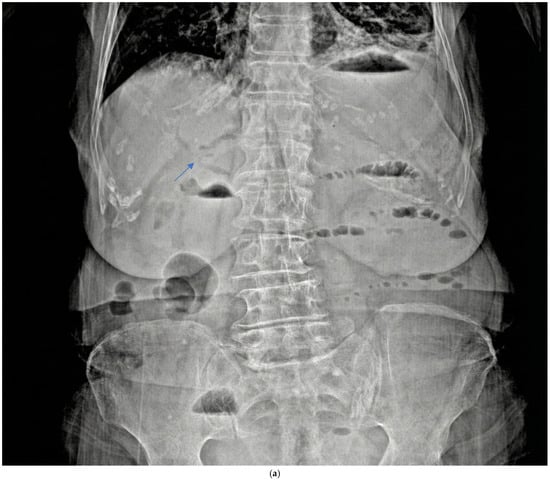

Preoperative imaging confirmed GI in all patients (Table 2). All patients had CT and plain X-ray, but none had a preoperative USG in the emergency department. CT revealed a bilioenteric fistula in all cases (12/12) (Figure 3b) and Rigler’s triad in 11/12 patients (91.7%). Air-fluid level and small bowel dilatation > 3 cm were seen in 11/12 patients (91.7%) (Figure 3c); one patient had stone impaction in the duodenum and did not show an air-fluid level. Free fluid was present in 4/12 patients (33.3%), suggesting potential peritonitis. The mean number of stones was 1.6 ± 1.2 (range 1–4), with a mean stone size of 3.19 ± 0.6 cm (range 2.6–5). The stones were primarily located in the distal ileum in 8/12 patients (66.7%) (Figure 3d). Plain X-ray showed an air-fluid level in 11/12 patients (91.7%) and pneumobilia in 2/12 patients (16.7%) (Figure 3a). Previous abdominal surgeries were found in 5/12 patients (41.67%).

Figure 3.

Radiologic images (a) plain X-ray air fluid level and pneumobilia (arrow). (b) Ct-scan bilioenteric fistula and stone (arrow). (c) ileus. (d) terminal ileum gallstone (arrow).

In our study, all 12 patients underwent CT, and Rigler’s triad was identified in 91.7% of patients, a rate substantially higher than the traditionally reported rates, reflecting CT’s superior sensitivity compared to X-ray. Small bowel dilatation exceeding 3 cm and air-fluid levels were seen in 91.7% of patients (n = 11/12); one patient with duodenal stone impaction did not show an air-fluid level. In our series, 66.7% of stones were located in the distal ileum, consistent with the literature. Only one patient had a stone impacted in the duodenum, representing Bouveret’s syndrome, which accounts for less than 10% of GI cases [4]. None of our patients underwent preoperative USG, which aligns with current practice favoring CT in emergency presentations.